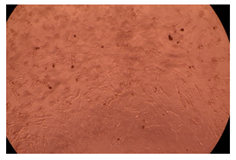

2.4. In Vitro Cytotoxicity Analysis

| Control |  |  | |

| Cop B | 10 µg/mL |  |  |

| 50 µg/mL |  |  | |

| 100 µg/mL |  |  | |

| Cop B/IMC = 10/1 (wt/wt) | 10 µg/mL |  |  |

| 50 µg/mL |  |  | |

| 100 µg/mL |  |  | |

| Cop B/Dorzolamide = 10/1 (wt/wt) | 10 µg/mL |  |  |

| 50 µg/mL |  |  | |

| 100 µg/mL |  |  | |